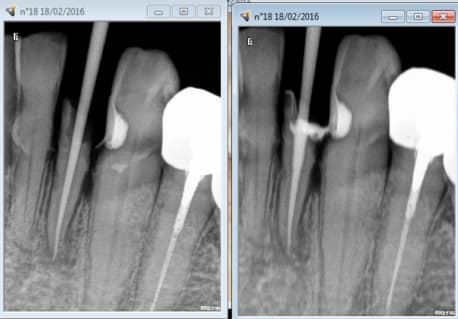

Exemple .

Radio de diagnostic le 01 12 2015, 32 à dévitaliser.

Le patient :" Ah non j'ai pas mal"

Vu aujourd'hui en urgence. Pulpite si si si dent vivante-)

Radios per et finale ( cone en place et cone scellé) gratuites. -)

Crampons de digue sur 36 et 46. -)

Jusqu'Ă  la preuve du contraire que je ne vais pas fournir. -)

Capture d e cran 2016 02 18 13.32 - Eugenol

Capture d e cran 2016 02 18 13.33 - Eugenol

Capture d e cran 2016 02 18 13.38 - Eugenol